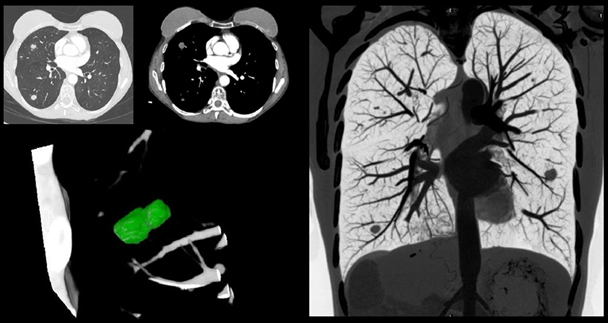

高端電腦斷層-低輻射劑量肺部掃描

影像醫學科主治醫師/吳汝濱

診斷肺癌的利器,早期發現、早期治療

低輻射劑量肺部掃描

日本研究證明發現,低劑量肺部電腦斷層掃描檢查,對於偵測非鈣化之肺小結節,有高於一股胸部X光 4~10 倍以上之偵測率。在美國有另一研究發現:在1000 人中,經低劑量肺部螺旋電腦斷層掃描後有27 人發現肺癌:而胸部 X光只發現7人。這是因為低劑量肺部電腦斷層掃檢查不僅比一般胸部X光有更高的偵測率,而且檢查時間快,不須注射顯影劑,更重要的是它的輻射劑量比一般的傳統電腦斷層要低上許多。

有鑒於此本院即將引進新一代高端電腦斷層掃描儀來雲、嘉地區民眾。本院引進機型施做低劑量肺部電腦斷層檢查優點在於:

• 檢測小於1公分以下(0.3-0.4以上)的病灶,以及檢查隱藏在心臟前後、橫膈膜上方、肋骨和肝臟前後方等較難在X光片上發現的病灶。

• 最新型電腦掃描肺部劑量可低至<1mSv,與一般的胸部X光檢查劑量相差無幾。

• 不需禁食、不需注射顯影劑的極細層切面檢查,以更高的影像解析,配合縱切面(冠狀位)影像,可以提供細小肺部結節的早期診斷。